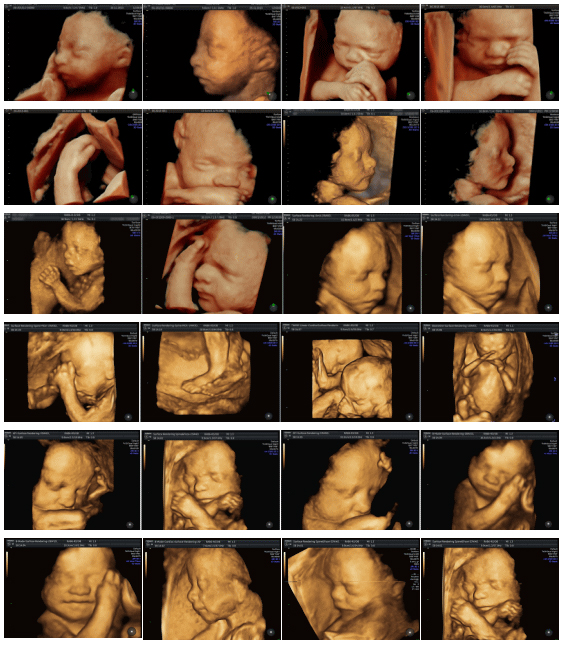

4Dエコー撮影した赤ちゃんの様子

子宮の中でどんな姿勢をしているのか?何をしているのか?寝ているのか?起きているのか?

あくびしている様子や、まばたきや、指しゃぶりをしている様子が見えることもあります。

ずっと後ろを向いていて、後頭部しか見えないことや、顔が隠れていて、脇やおまたの一部しか見えないこともよくあります。

それでもかわいらしさが、4Dエコーを通して伝わってきます。